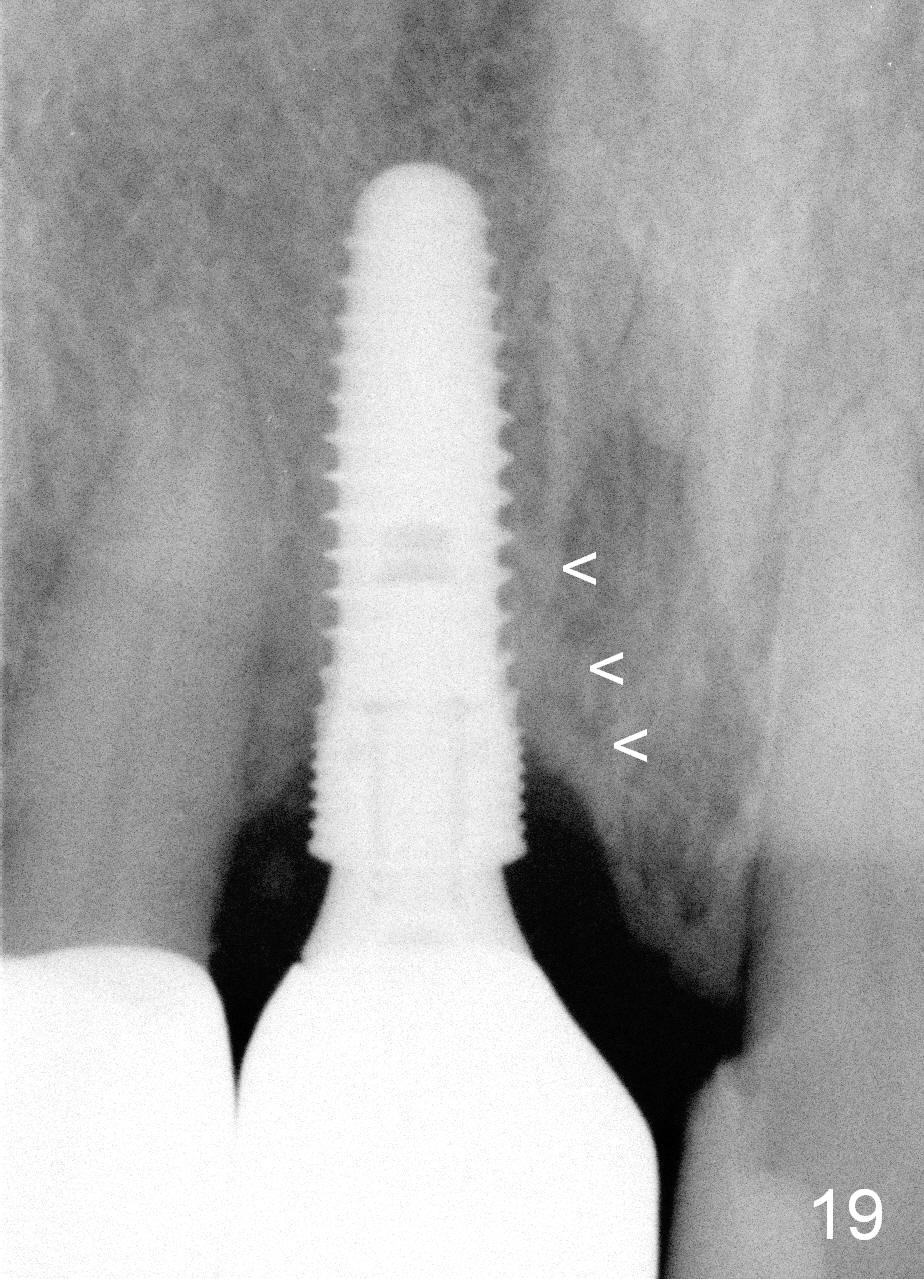

One year post cementation, there is cortical bone formation mesial to the implant (Fig.19 <). Buccal concavity is minimal (Fig.20).